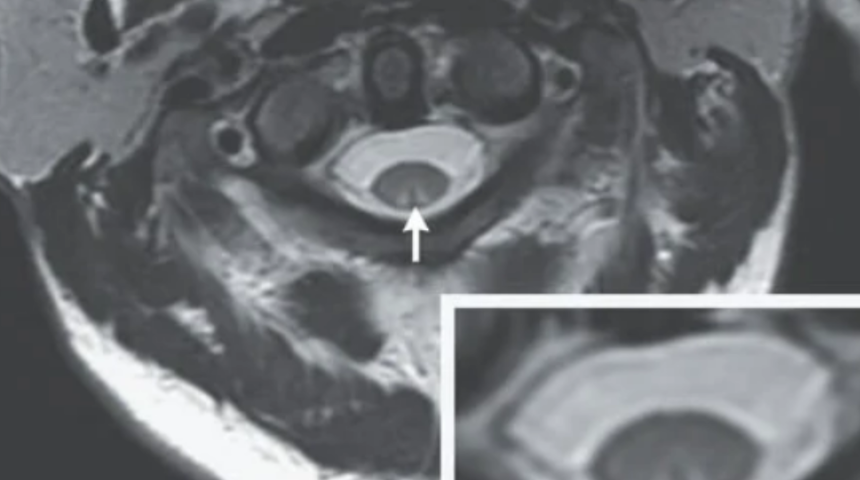

Yapılan MRI taramasında omuriliğinin bazen B12 vitamini eksikliğinden kaynaklanan miyelopati olarak bilinen nörolojik bir durumun belirtilerini göstermeye başladığını ortaya çıkardı. Bu, omuriliğin çevredeki bölgelerdeki iltihaplanma ile sıkıştırılmasıyla olur. Tedavi edilmezse miyelopati, felç ve hatta ölüm dahil olmak üzere önemli ve kalıcı sinir hasarına yol açabilir.

Doktorlar ayrıca, omuriliğin bir kısmının, dokunma hissinden sorumlu olan dorsal kolonun kötü şekilde yaralandığını ve taramaların gelişmekte olan bir lezyonu ortaya çıkardığını buldular. Nitröz oksitin uzun süreli kullanımının B12 vitamini eksikliğine neden olduğu bilinmektedir. Bu, sinir hasarı ve omuriliğin dejenerasyonu gibi nörolojik sorunlara neden olabilir.